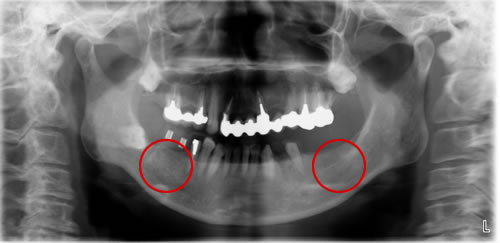

Before

治療前のエックス線です。赤丸に埋入予定です。